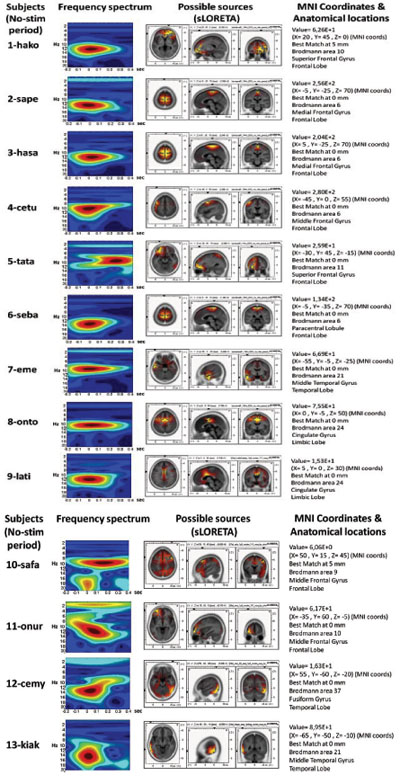

Spontaneous (Unevoked) Spindle Oscillation Activity

The source localization revealed BA6 as the major current density maxima in 6 out of 9 patients. The level of the propofol anesthesia is over the range of 1.2 µg/mL for these data sets (which coincided with the loss of consciousness). The spontaneous activity from every participant of the current study is included in the Appendix. The left column denotes the spectrograms. The sLORETA images and the maxima 3D coordinates as well as the Broadman areas are also provided. The locations from the maximal activity areas include, BA6 (5 subjects), BA9, BA10 (2 subjects), BA21 (2 subjects), BA24 (2 subjects), BA37. A sample is provided in Fig. (4), which presents activity at BA6 for the spindle oscillations during an unevoked condition.

APPENDIX

The sLORETA and Corticograms from single subjects